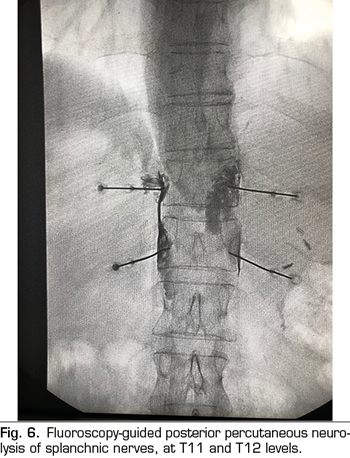

Figure 6